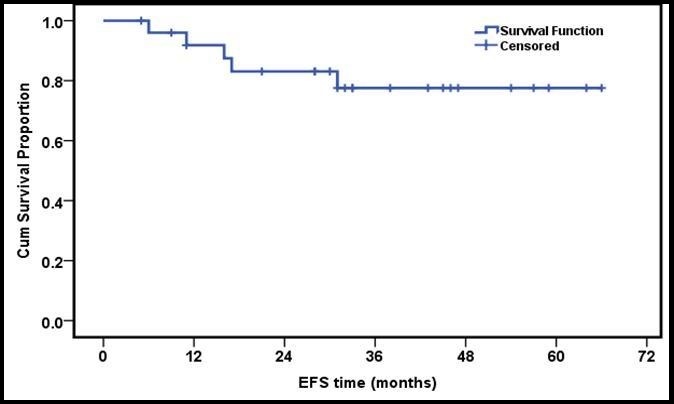

The 3 year estimated OS and EFS rates were 83.3% and 80.7% respectively (Figure 1 and Figure 2).

Figure 2.3 years EFS of the whole group of patients

The 3 year estimated OS and EFS rates were 83.3% and 80.7% respectively, that was similar to what has been reported by other groups 28, 29, 30